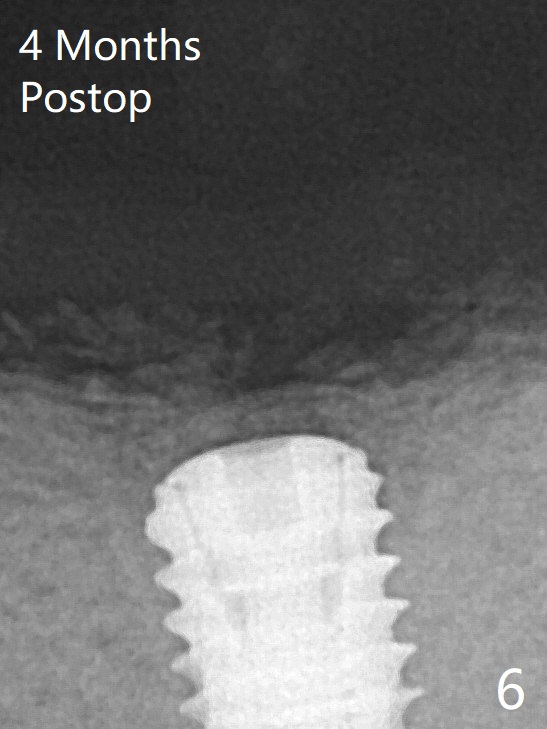

A 4.5x7.3 mm implant is initiatlly placed (Fig.3). The coronal defect is filled with allograft (Fig.4 *) following further placement of the implant. There is reorganized bone coronal to the healing screw 4 months postop (Fig.6), which is confirmed in uncovering. The overlying bone should be removed thoroughly for complete abutment seating.